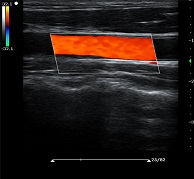

? ?● 多種成像模式

? ? ? ?B、C、PW、CW、BCD三功、大角度偏轉(zhuǎn)成像、實(shí)時(shí)寬景成像、梯形成像(僅支持線陣)、解剖M型、彩色M型成像、組織多普勒成像、3D/4D成像

? ?● 彩色多普勒增強(qiáng)技術(shù)

? ? ? ?有效抑制彩色血流閃動(dòng)噪聲,提高血流分辨率和靈敏度